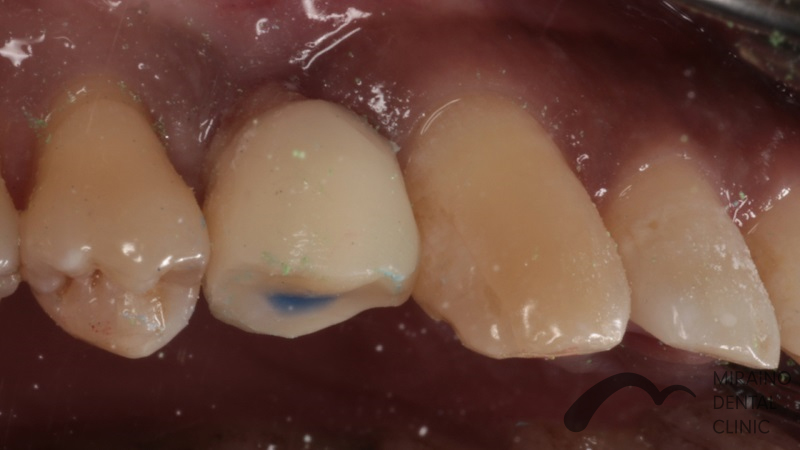

外傷の症例

Case1

| 施術名 | 外傷・神経の保存 |

| 治療の概要 | 仕事中の事故により歯が欠けて来院されました。 神経まで露出しており従来の治療基準では神経を取らねばなりませんが、 神経を残す新しい材料MTAにより神経を保存する治療を行いました。 3ヶ月経過観察後、歯の神経の感染壊死の症状が見られなかったため、 神経を残しながら汚れのつきにくい素材で被せ物を装着しました。 |

クリックして詳細を表示

| 施術の内容 | 歯の神経が見えてしまった際に抗菌作用の材料MTAで神経を温存する治療です。 ラバーダムを用いて唾液による感染のリスクを排除し無菌的な治療を行います。 |